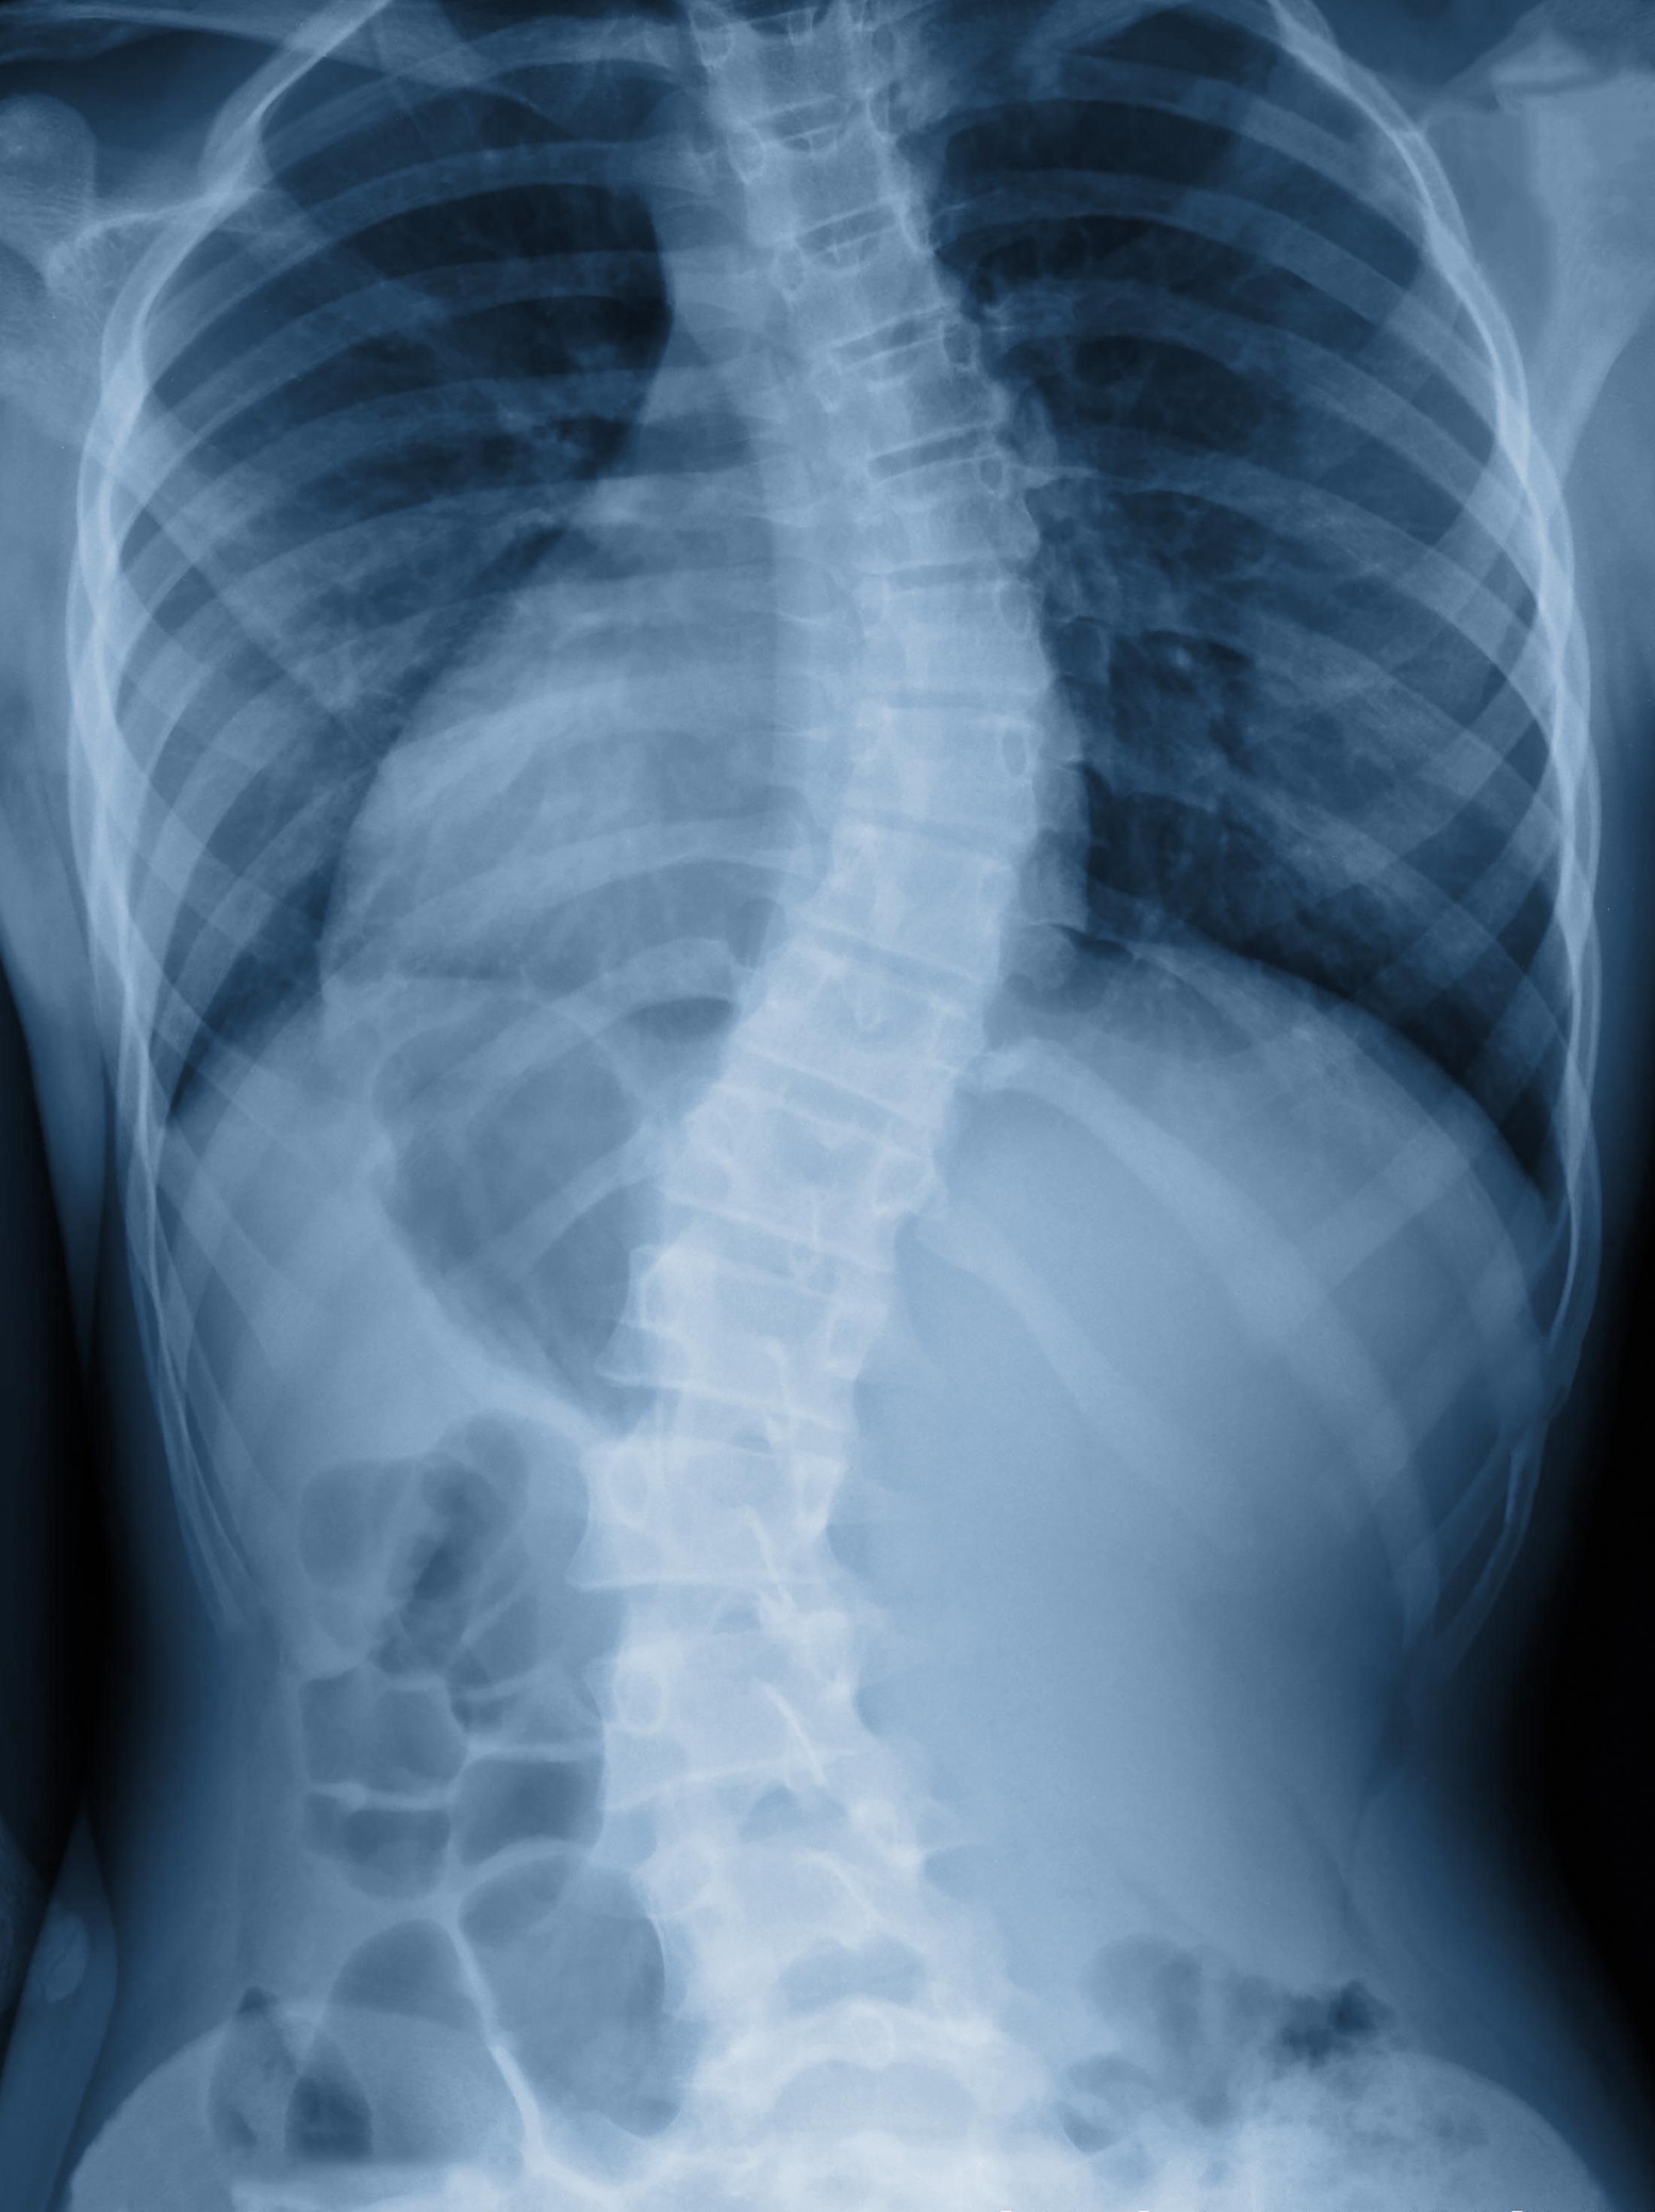

اعوجاج العمود الفقري لا يكون دائمًا انحناءة واحدة فقط. في بعض الحالات يكون هناك انحناء واحد بسيط، وفي حالات أخرى يكون هناك انحناءان أو أكثر في اتجاهات مختلفة.

عدد الانحناءات يعني عدد المناطق التي يخرج فيها العمود الفقري عن شكله المستقيم الطبيعي عند النظر إليه من الخلف.

يكون العمود الفقري منحنيًا في اتجاه واحد فقط، وغالبًا يكون شكله أقرب إلى حرف C.

يظهر العمود الفقري بشكل أقرب إلى حرف S، حيث يعوض الجسم انحناءً بانحناء آخر للحفاظ على التوازن.

الطريقة الوحيدة الدقيقة لمعرفة عدد الانحناءات هي الفحص الطبي المدعوم بالأشعة.

الأشعة السينية

الأشعة السينية هي الأساس في تحديد:

موقع كل انحناء (صدري، قطني، أو مختلط)

اتجاه الانحناء

درجة كل انحناء على حدة

من خلال الأشعة يمكن رؤية العمود الفقري بالكامل وتحديد كل انحناء بوضوح.